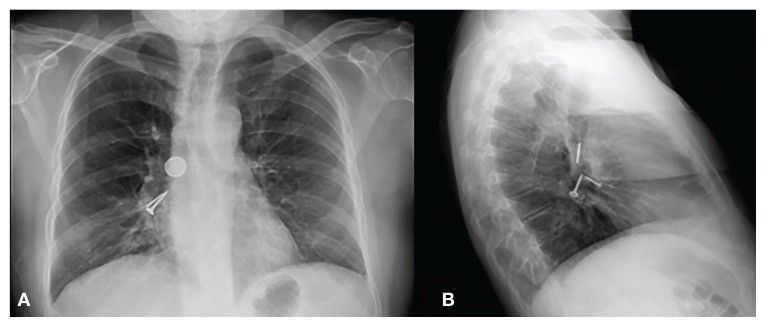

У 55-летнего мужчины в течение месяца были жалобы на кашель, одышку и дисфагию. В связи с ухудшением самочувствия он был доставлен в стационар. При осмотре его состояние было стабильным, а SpO2 — 97%. При аускультации выслушивались двусторонние рассеянные хрипы. В общем анализе крови отмечен лейкоцитоз со сдвигом формулы влево. При рентгенографии органов грудной клетки в проекции правого главного бронха обнаружены три металлических предмета: 1 круглый и 2 плоских — винт и гвоздь (рис. 1).

Рисунок 1 [1].